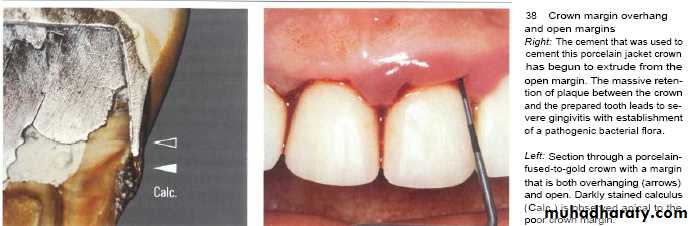

1-Margins of restoration:

• Overhanging margins induce plaque accumulation & change

• the environment that allows growth of pathogenic bacteria &

• inhibit patient access to remove plaque.

2- Exposed rough surface of prepared tooth between crown margin & finishing line (luting agent).

3- Disintegration of luting agent lead to crater formation.

4- Inadequate marginal fitness of restoration.

Subgingival margins typically have a gap of 20 to 40 microns between the margin of the restoration and the unprepared tooth.

Marginal fit has close relation with an inflammatory response in the periodontium.

It has been shown that the level of gingival inflammation can increase with increasing level of marginal opening.

Margins that are significantly open are capable of harboring large numbers of bacteria and may be responsible for the inflammatory response .